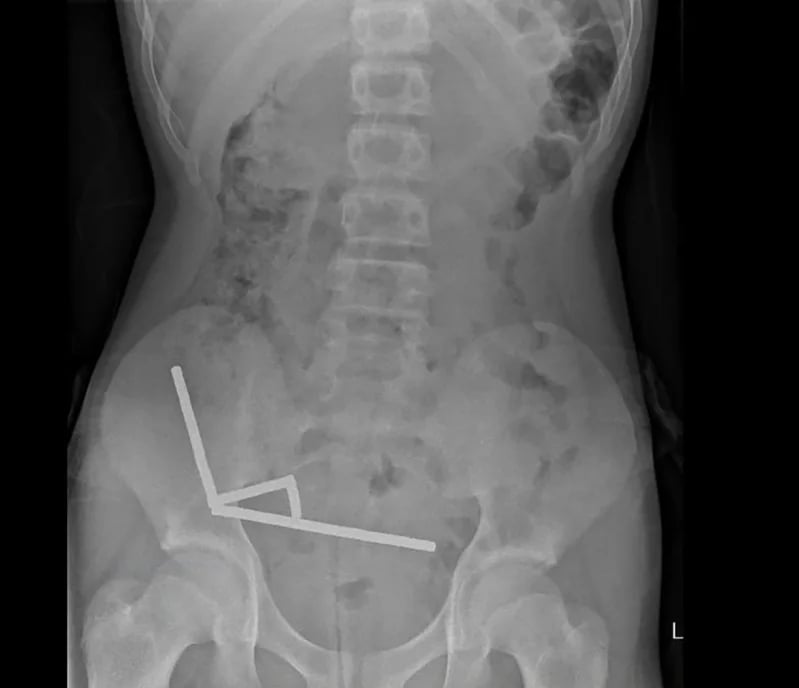

在這張紐西蘭醫學期刊(NZMJ)24日發布的未註明日期新聞照片中,X光片顯示一名青少年腸道內聚集成4條直線的強力磁鐵。法新社

儘管紐西蘭早在2013年1月就已禁止釹磁鐵銷售,但男孩仍透過線上購物平台Temu取得。X光顯示,磁鐵在男孩腸道內排列成4條直線。報告指出:「這些磁鐵位於腸道的不同部位,但因磁力作用而使各段腸道彼此沾黏。」